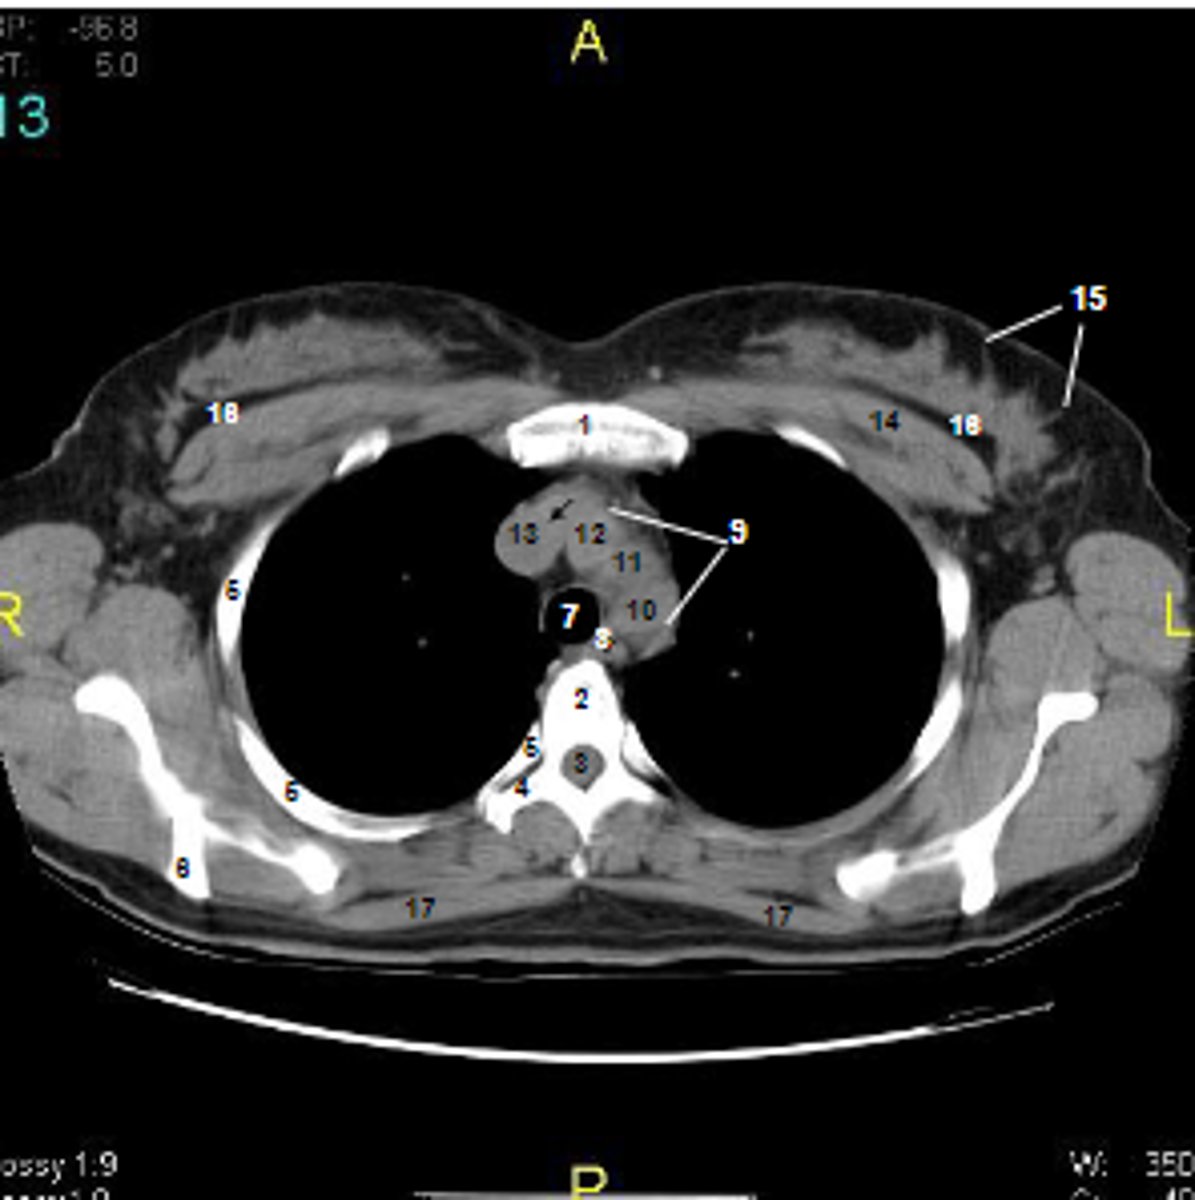

1

at what number is the sternum

2

at what number is the vertebral body

3

at what number is the vertebral canal/ spinal cord

4

at what number is the transverse process of vertebra

5

at what number is the rib

6

at what number is the spine of scapula

7

at what number is the trachea

8

at what number is the esophagus

9

at what number is the arch of aorta

10

at what number is the left subclavian artery

11

at what number is the common carotid artery

12

at what number is the brachiocephalic trunk

13

at what number is the superior vena cava

14

at what number is pectoralis major

15

at what number are Cooper's ligaments

16

at what number is the retromammary space

17

at what number is trapezius